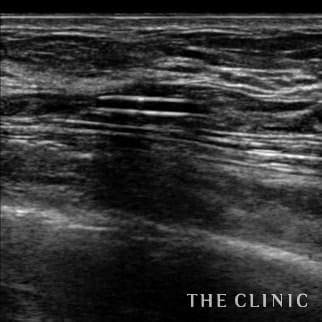

35歳 女性 アクアフィリング(アクアリフト)豊胸のお悩みのアクアフィリング(アクアリフト)豊胸除去

コンデンスリッチ豊胸を行うために、前もってアクアフィリングの除去を行いました。エコーで確認するとかなり厚い被膜が形成されています。 アクアフィリングは生理食塩水で溶解されるとのことで、エコー下に生理食塩水を注入しましたが、なかなか溶解できず、ヒアルロニダーゼも追加してなんとか溶解除去することができました。右側は炎症があった為か、汚く濁った状態でした。治療の概要 アクアフィリング除去+コンデンスリッチ豊胸:乳腺用エコーを用いて、バスト内の状態を確認。その後、生理食塩水でアクアフィリングを溶解する。溶解仕切れない場合には、注射器で吸い出し除去。アクアフィリング の除去後、バストの皮下にコンデンスリッチファット(老化細胞や不純物を取り除いて濃縮させた自己脂肪)を注入。 施術費用 アクアフィリング 除去(会員料金):¥600,000(税込¥660,000)/溶解1部位